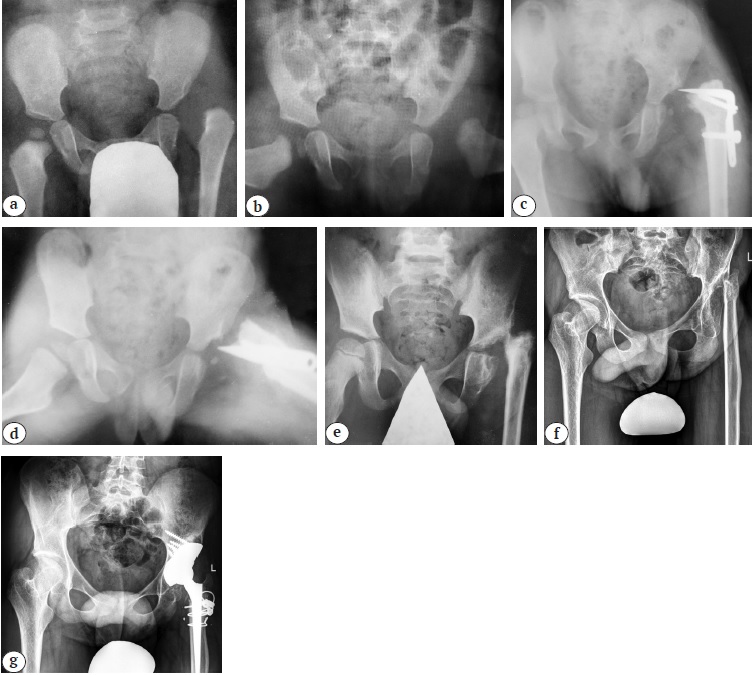

В настоящем исследовании средний возраст 72 (13,6%) пациентов с последствиями перенесенного ЮЭГБК на момент госпитализации в клинику составил 15,9±1,8 лет. Сбор анамнестических данных позволил установить, что 65 (90,3%) детям проводилось хирургическое лечение, причем однократное. У 7 (9,7%) пациентов правильный диагноз не был установлен, из них у 2 детей имело место двустороннее поражение. При планировании ТЭТС у всех пациентов отмечались рентгенологические признаки либо асептического некроза головки бедренной кости с ее грубой деформацией, либо хондролиза вертлужной впадины, за исключением пациентов, не получавших лечения. Изучение характера проведенных операций при различных стадиях и течении заболевания позволило определить причины развития терминальной стадии коксартроза. Так, 16 (25%) пациентам с острым смещением проксимального эпифиза бедренной кости проводилась одномоментная закрытая репозиция с фиксацией спицами на сроке от 5 до 7 сут. после госпитализации пациента в стационар. Необходимо отметить, что у всех этих пациентов острое смещение произошло на фоне хронического. При этом в медицинской документации упоминаний о проведении дренирующих тазобедренный сустав манипуляций (пункция или капсулотомия) нами не было обнаружено. Кроме того, у 11 из 16 пациентов выявлены выраженное остаточное смещение эпифиза и мальпозиция металлофиксаторов в виде их пенетрации в полость сустава (рис. 7).

Рис. 7. Серия рентгенограмм тазобедренных суставов пациента 14 лет с левосторонним коксартрозом 3 стадии в результате лечения ЮЭГБК: a, b — через 6 мес. после выполнения закрытой репозиции с фиксацией пучком спиц (отмечается неустраненное смещение головки бедренной кости по отношению к шейке со значительным сужением суставной щели и мальпозицией спицы Киршнера); c — непосредственно перед проведением эндопротезирования (помимо классических признаков коксартроза 3 стадии, отмечаются характерные для хондролиза вертлужной впадины ее протрузия с краниальном смещением головки бедренной кости); d — среднесрочный результат выполнения тотальной бесцементной артропластики системой Zimmer Biomet (чашка Trilogy IT® 62 мм; ножка Alloclassic® 6, пара трения — керамика — поперечносвязанный полиэтилен) c аутопластикой дна вертлужной впадины

Fig. 7. X-ray series of a 14-years-old patient with 3 grade left-sided hip osteoarthritis as a result of SCFE treatment: a, b — X-ray of the hip joints 6 months after closed reduction with a K-wires fixation (accompanied by uncorrected displacement of the femoral head relative to the femoral neck with a significant joint space and malposition of the K-wires); c — X-ray of the hip joints just before THA (in addition to the classic signs of 3 grade hip osteoarthritis, typical for acetabulum chondrolysis protrusion with cranial displacement of the femoral head is observed); d — mid-term result of THA performed with the Zimmer Biomet system (Trilogy IT® 62 mm cup; Alloclassic® 6, ceramic-crosslinked polyethylene) and autoplasty of the acetabular floor

Из 49 (75%) пациентов с хроническим течением заболевания и смещением эпифиза кзади на 30° и более внесуставная вальгизирующая остеотомия бедренной кости была выполнена в 42 случаях, а внутрисуставные остеотомии (корригирующая трансцервикальная остеотомия или модифицированная операция Dunn) — в 7. Изучение серии рентгенограмм данной категории пациентов после хирургического лечения позволило определить причину развития терминальной стадии артроза тазобедренного сустава. Так, у пациентов с коррекцией пространственного положения смещенного эпифиза путем выполнения околосуставной остеотомии бедренной кости коксартроз развился в результате ротации проксимального отдела кпереди на величину более 45° (рис. 8).

Рис. 8. Серия рентгенограмм тазобедренных суставов пациента 16 лет с правосторонним коксартрозом 3 стадии в результате лечения ЮЭГБК: a, b — рентгенограммы в переднезадней и аксиальной проекциях на момент первичного обращения в один из стационаров (смещение головки правой бедренной кости кзади на 50°); c, d — рентгенограммы в переднезадней и аксиальной проекциях непосредственно после проведения ротационной остеотомии бедренной кости с остеосинтезом пластиной с угловой стабильностью (восстановлены пространственные соотношения в системе «вертлужная впадина — головка — шейка бедренной кости» за счет ротации проксимального отдела кпереди в горизонтальной плоскости на 50°); e — через полтора года после проведения первичного хирургического лечения (признаки терминальной стадии коксартроза с подвывихом бедра); f — среднесрочный результат тотального эндопротезирования системой Zimmer Biomet (чашка Trilogy IT® 52 мм; ножка Alloclassic® 4, пара трения: керамика — поперечносвязанный полиэтилен) c аутопластикой свода вертлужной впадины

Fig. 8. X-ray series of a 16-years-old patient with 3 grade right-sided osteoarthritis as a result of SCFE treatment: a, b — X-rays of the hip joints in the anteroposterior and axial views at the time of initial admission (a posterior displacement of the head of the right femur by 50° is observed); c, d — X-rays of the hip joints in the anteroposterior and axial views just after rotational femoral osteotomy and osteosynthesis performed with an angle stable plate (spatial relations in the “acetabulum — femoral head — femoral neck” system are restored due to anterior rotation of the proximal part in horizontal plane by 50°); e — X-ray of the hip joints in a year and a half after primary surgical treatment (signs of end-stage hip osteoarthritis with hip subluxation are observed); f — mid-term result of THA performed with the Zimmer Biomet system (Trilogy IT® 52 mm cup; Alloclassic® 4, ceramic-crosslinked polyethylene) and autoplasty of the acetabular arch

У всех пациентов, которым выполняли внутрисуставные остеотомии, диагностирован асептический некроз головки бедренной кости с ее грубой деформацией, который развился в связи c нарушением артериальной перфузии головки бедренной кости (рис. 9).

Рис. 9. Серия рентгенограмм тазобедренных суставов пациента 16 лет с левосторонним коксартрозом 3-й стадии в результате лечения ЮЭГБК: a, b — рентгенограммы в переднезадней и аксиальной проекциях на момент первичного обращения в один из стационаров (смещение головки правой бедренной кости кзади на 63° с формированием остеофита в месте перехода «головка — шейка», признаки синтозирования физарного хряща эпифиза); c, d — рентгенограммы в переднезадней и аксиальной проекциях непосредственно после проведения внутрисуставной корригирующей остеотомии шейки бедренной кости (восстановлены пространственные соотношения в системе «вертлужная впадина — головка — шейка бедренной кости»); e — через год после проведения первичного хирургического лечения (признаки асептического некроза головки бедренной кости с ее грубой многоплоскостной деформацией и подвывихом бедра); f — среднесрочный результат тотального эндопротезирования системой Zimmer Biomet (чашка Trilogy IT® 48 мм; ножка Alloclassic® 5, пара трения керамика — поперечносвязанный полиэтилен)

Fig. 9. X-ray series of a 16-years-old patient with 3 grade left-sided osteoarthritis as a result of SCFE treatment: a, b — X-rays of the hip joints in the anteroposterior and axial views at the time of initial admission (a posterior displacement of the head of the right femur by 63° with developing osteophyte at the “head-neck” junction and signs of the epiphysial cartilage formation are observed); c, d — X-rays of the hip joints in the anteroposterior and axial views just after intraarticular corrective osteotomy of the femoral neck (spatial relations in the “acetabulum — head — femoral neck” system are restored); e — X-rays of the hip joints in a year after primary surgical treatment (signs of aseptic necrosis of the femoral head with its gross multiplanar deformation and hip subluxation are observed); f — mid-term result of THA performed with the Zimmer Biomet system (Trilogy IT® 48 mm cup; Alloclassic® 5, ceramic-crosslinked polyethylene)